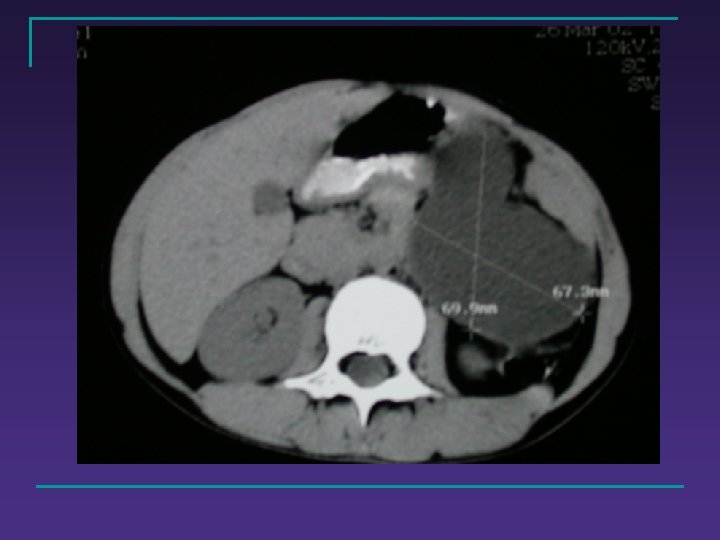

Diagnostic de certitude n n Évolution clinique +++ Faisceau d’arguments: q q Cliniques Radiographiques : n n q Echographie : infiltration ++ A. S. P Biologiques : n n G. B C. R. P